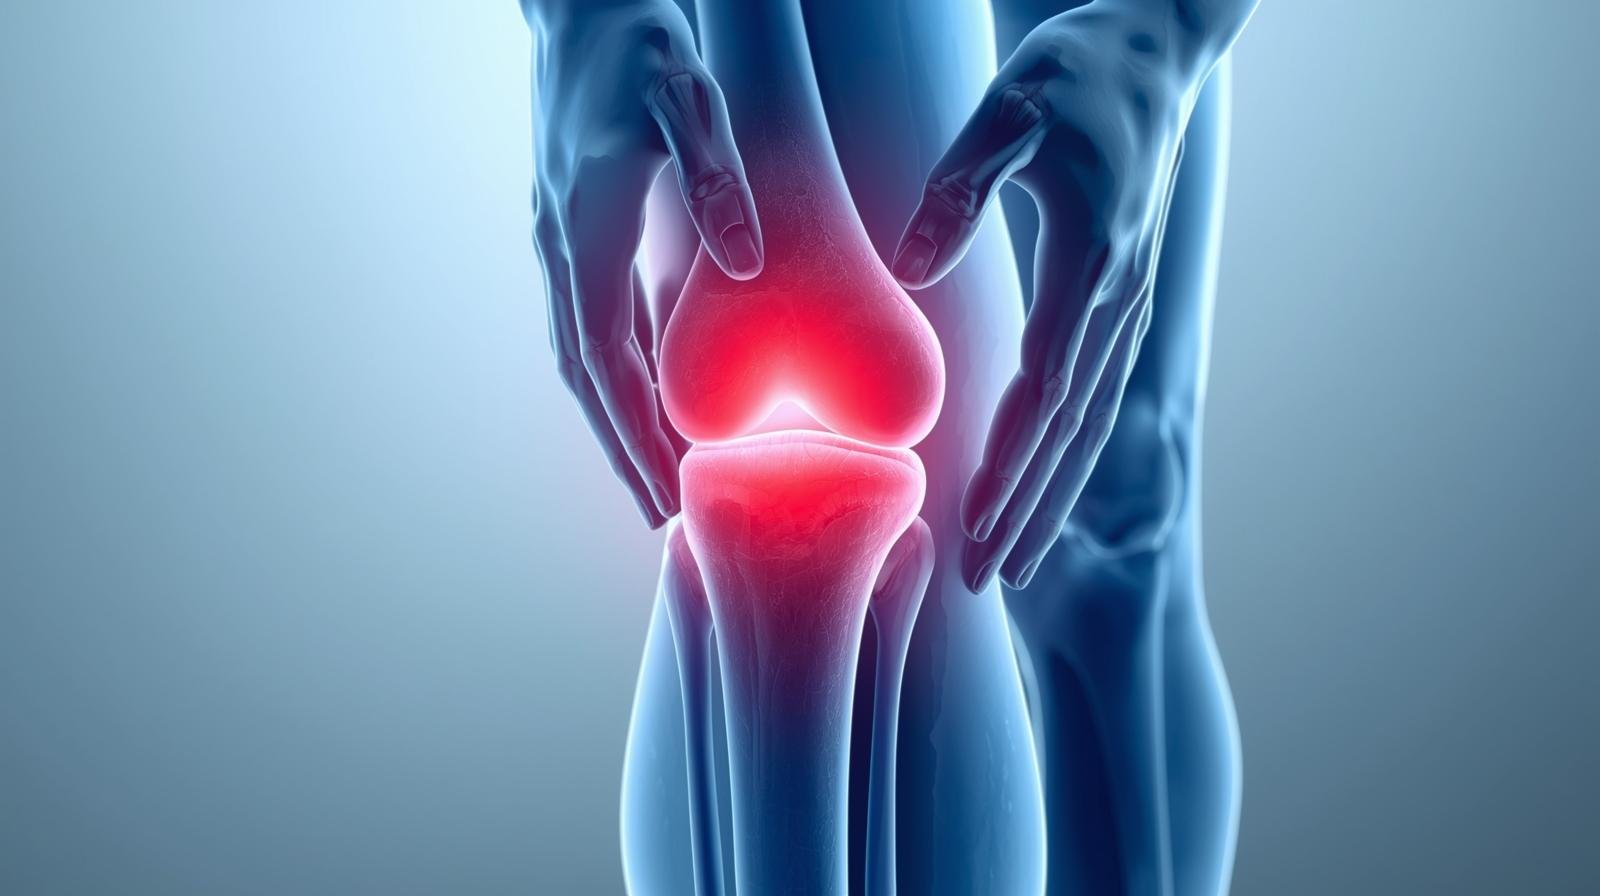

تعتبر التهابات المفاصل مصطلحاً عاماً يضم تحت مظلته مئات الحالات الطبية التي تسبب التورم والتيبس، مما يجعل المهام اليومية تبدو وكأنها معركة شاقة. ولأن التشخيص المبكر هو حجر الزاوية في تجنب تلف المفاصل المستديم، نقدم لك في هذا المقال مرجعاً متكاملاً حول مسببات الالتهاب، وكيف تفرق بين أنواعه المختلفة؟ وما هي أحدث بروتوكولات العلاج التي تدمج بين الطب الحديث ونمط الحياة الصحي للوقاية من مضاعفات المرض.

التهاب المفاصل مصطلح عام لمئات الحالات التي تسبب الألم والتيبس في المفاصل, التهابات المفاصل هي حالة مرضية تحدث نتيجة التهاب في واحد أو أكثر من المفاصل، مما يؤدي إلى الشعور بالألم، التورم، والتيبس، مع صعوبة في الحركة. وقد يكون الالتهاب ناتجًا عن سبب مناعي، عدوى، تآكل في الغضاريف، أو عوامل وراثية.

أعراض التهاب المفاصل تشمل الألم، التورم، الاحمرار، والتيبس في المفاصل، وقد يرافقها الإرهاق، الحمى، وفقدان الوزن، وتختلف شدة وتوقيت هذه الأعراض حسب نوع الالتهاب، مثل الفصال العظمي، الروماتويدي، أو الصدفي، وتؤثر أحيانًا على أجزاء أخرى من الجسم كالعينين والجلد.

تورم واحمرار: انتفاخ في المفصل واحمرار في المنطقة المحيطة به.